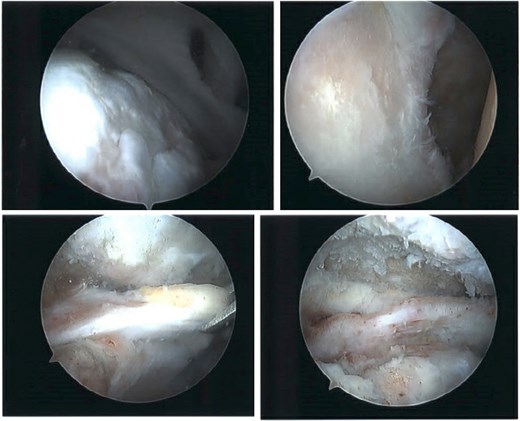

At 2-week follow-up, he reported continued shoulder pain. His right-sided paresthesias had resolved; however, he reported continued paresthesias into his left forearm and hand. He had significant bilateral limitation in range of motion, and weakness on internal and external rotation, more so on the left. Special tests included a positive Jobe test, drop arm test, belly press test, Obrien’s test, and Speed’s test bilaterally, as well as a positive left-sided bear hug test. He was advised to start gentle range of motion, avoid lifting, and was sent for bilateral shoulder MRIs (Figs 5 and 6).

MRI of the right shoulder demonstrating full-thickness tearing of the supraspinatus and infraspinatus with medial tendon retraction, a high riding humeral head, intermediate grade partial thickness tear of the teres minor, severe fatty atrophy of the subscapularis muscle belly, labral degeneration, and tearing, partial thickness tearing of the inferior glenohumeral ligament, anterior-inferior glenoid subchondral marrow edema, and severe glenohumeral cartilage abnormalities.

MRI of the left shoulder demonstrating a full-thickness tear of the supraspinatus and infraspinatus with tendon retraction, high grade partial thickness tearing of the subscapularis, full-thickness tear of the biceps long head tendon, complex anterior labrum tear, partial thickness tear of the inferior glenohumeral ligament including the anterior and posterior bands, inferior glenoid subchondral marrow edema, and moderate glenohumeral degenerative changes.